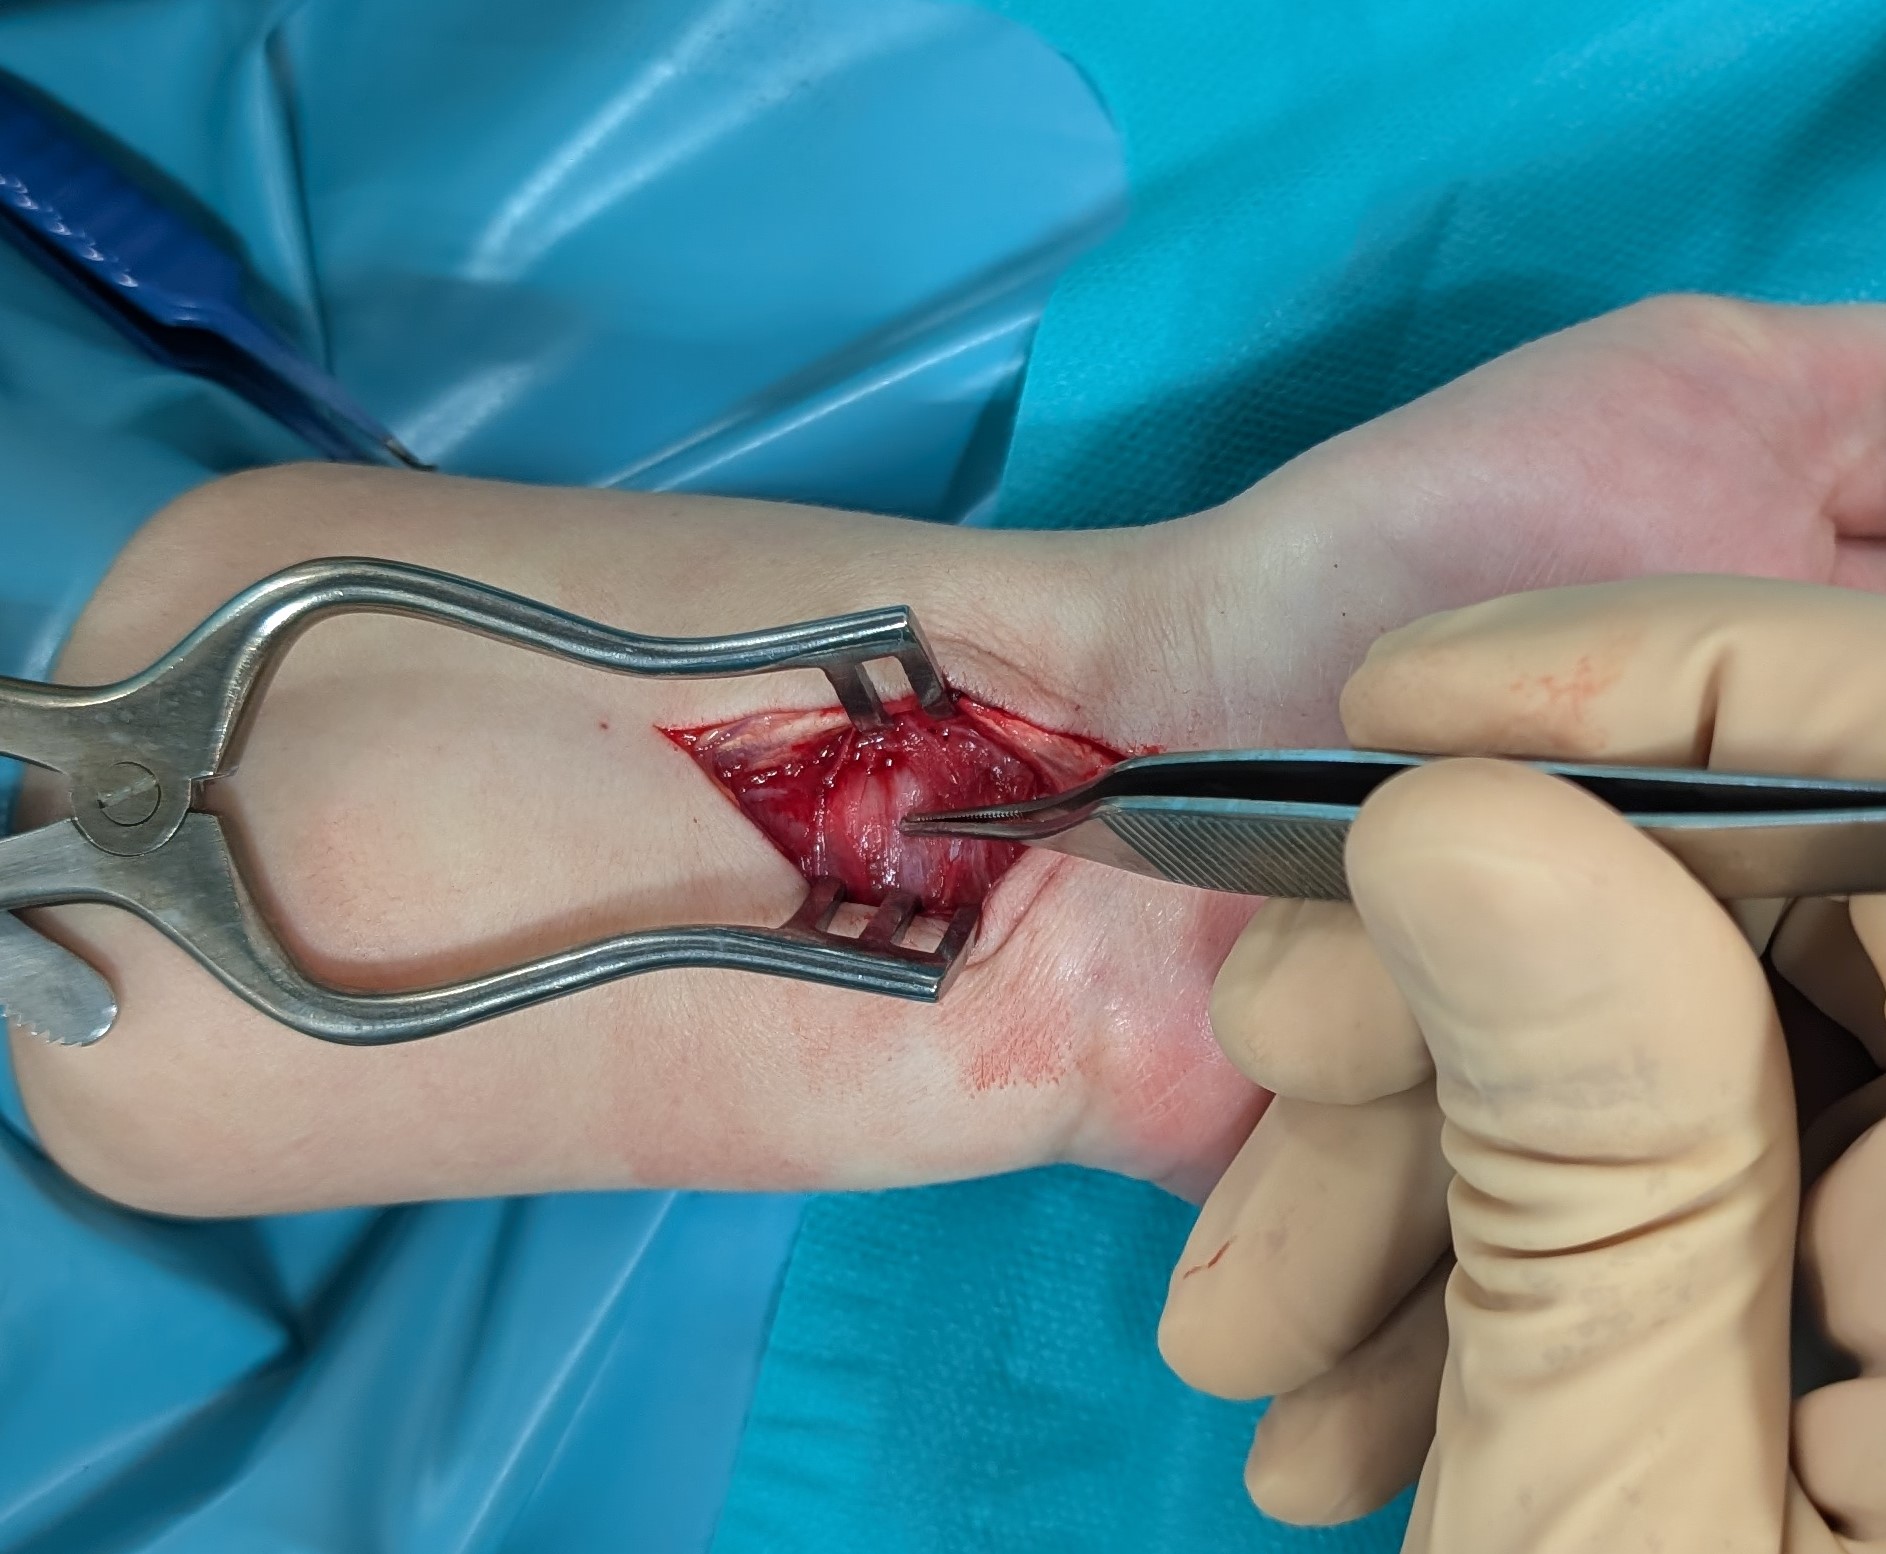

Enucleation of the median nerve tumour under WALANT: a case report

A case of a median nerve tumour (schwannoma) located in the distal part of the forearm, which was enucleated from the nerve under local anaesthesia (WALANT), without the use of a tourniquet on the arm to obtain a bloodless surgical field, is presented. To the best of the authors’ knowledge, this is the first described case of nerve tumour surgery under this anaesthesia. It shows that operation of nerve tumours can be performed under WALANT, without deteriorating of patients’ safety and surgeons comfort. The authors believe that presentation of this case can be interesting for hand surgeons and will encourage them to extend the scope of operations performed under WALANT.